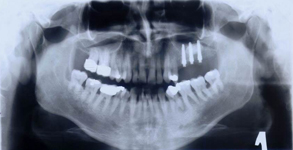

Velmi často je pro zavedení implantátu vzhledem k nedostatku kosti provést její doplnění tzv. augmentaci. Naše zařízení je zaměřené na doplnění nedostatečného množství kosti a používá celou řadu moderních postupů metod a matriálů. Velký význam pro úspěšné doplnění kosti hraje i dostatečné množství měkkých tkání – sliznice, která musí dodané množství kosti dokonale překrýt a nesmí ani tlakem způsobit jeho resorpci.

Jednou z nejmodernějších a velice šetrnou metodou pro získání dostatečného množství měkkých tkání je použití

osmotického hydrogelového expanderu.